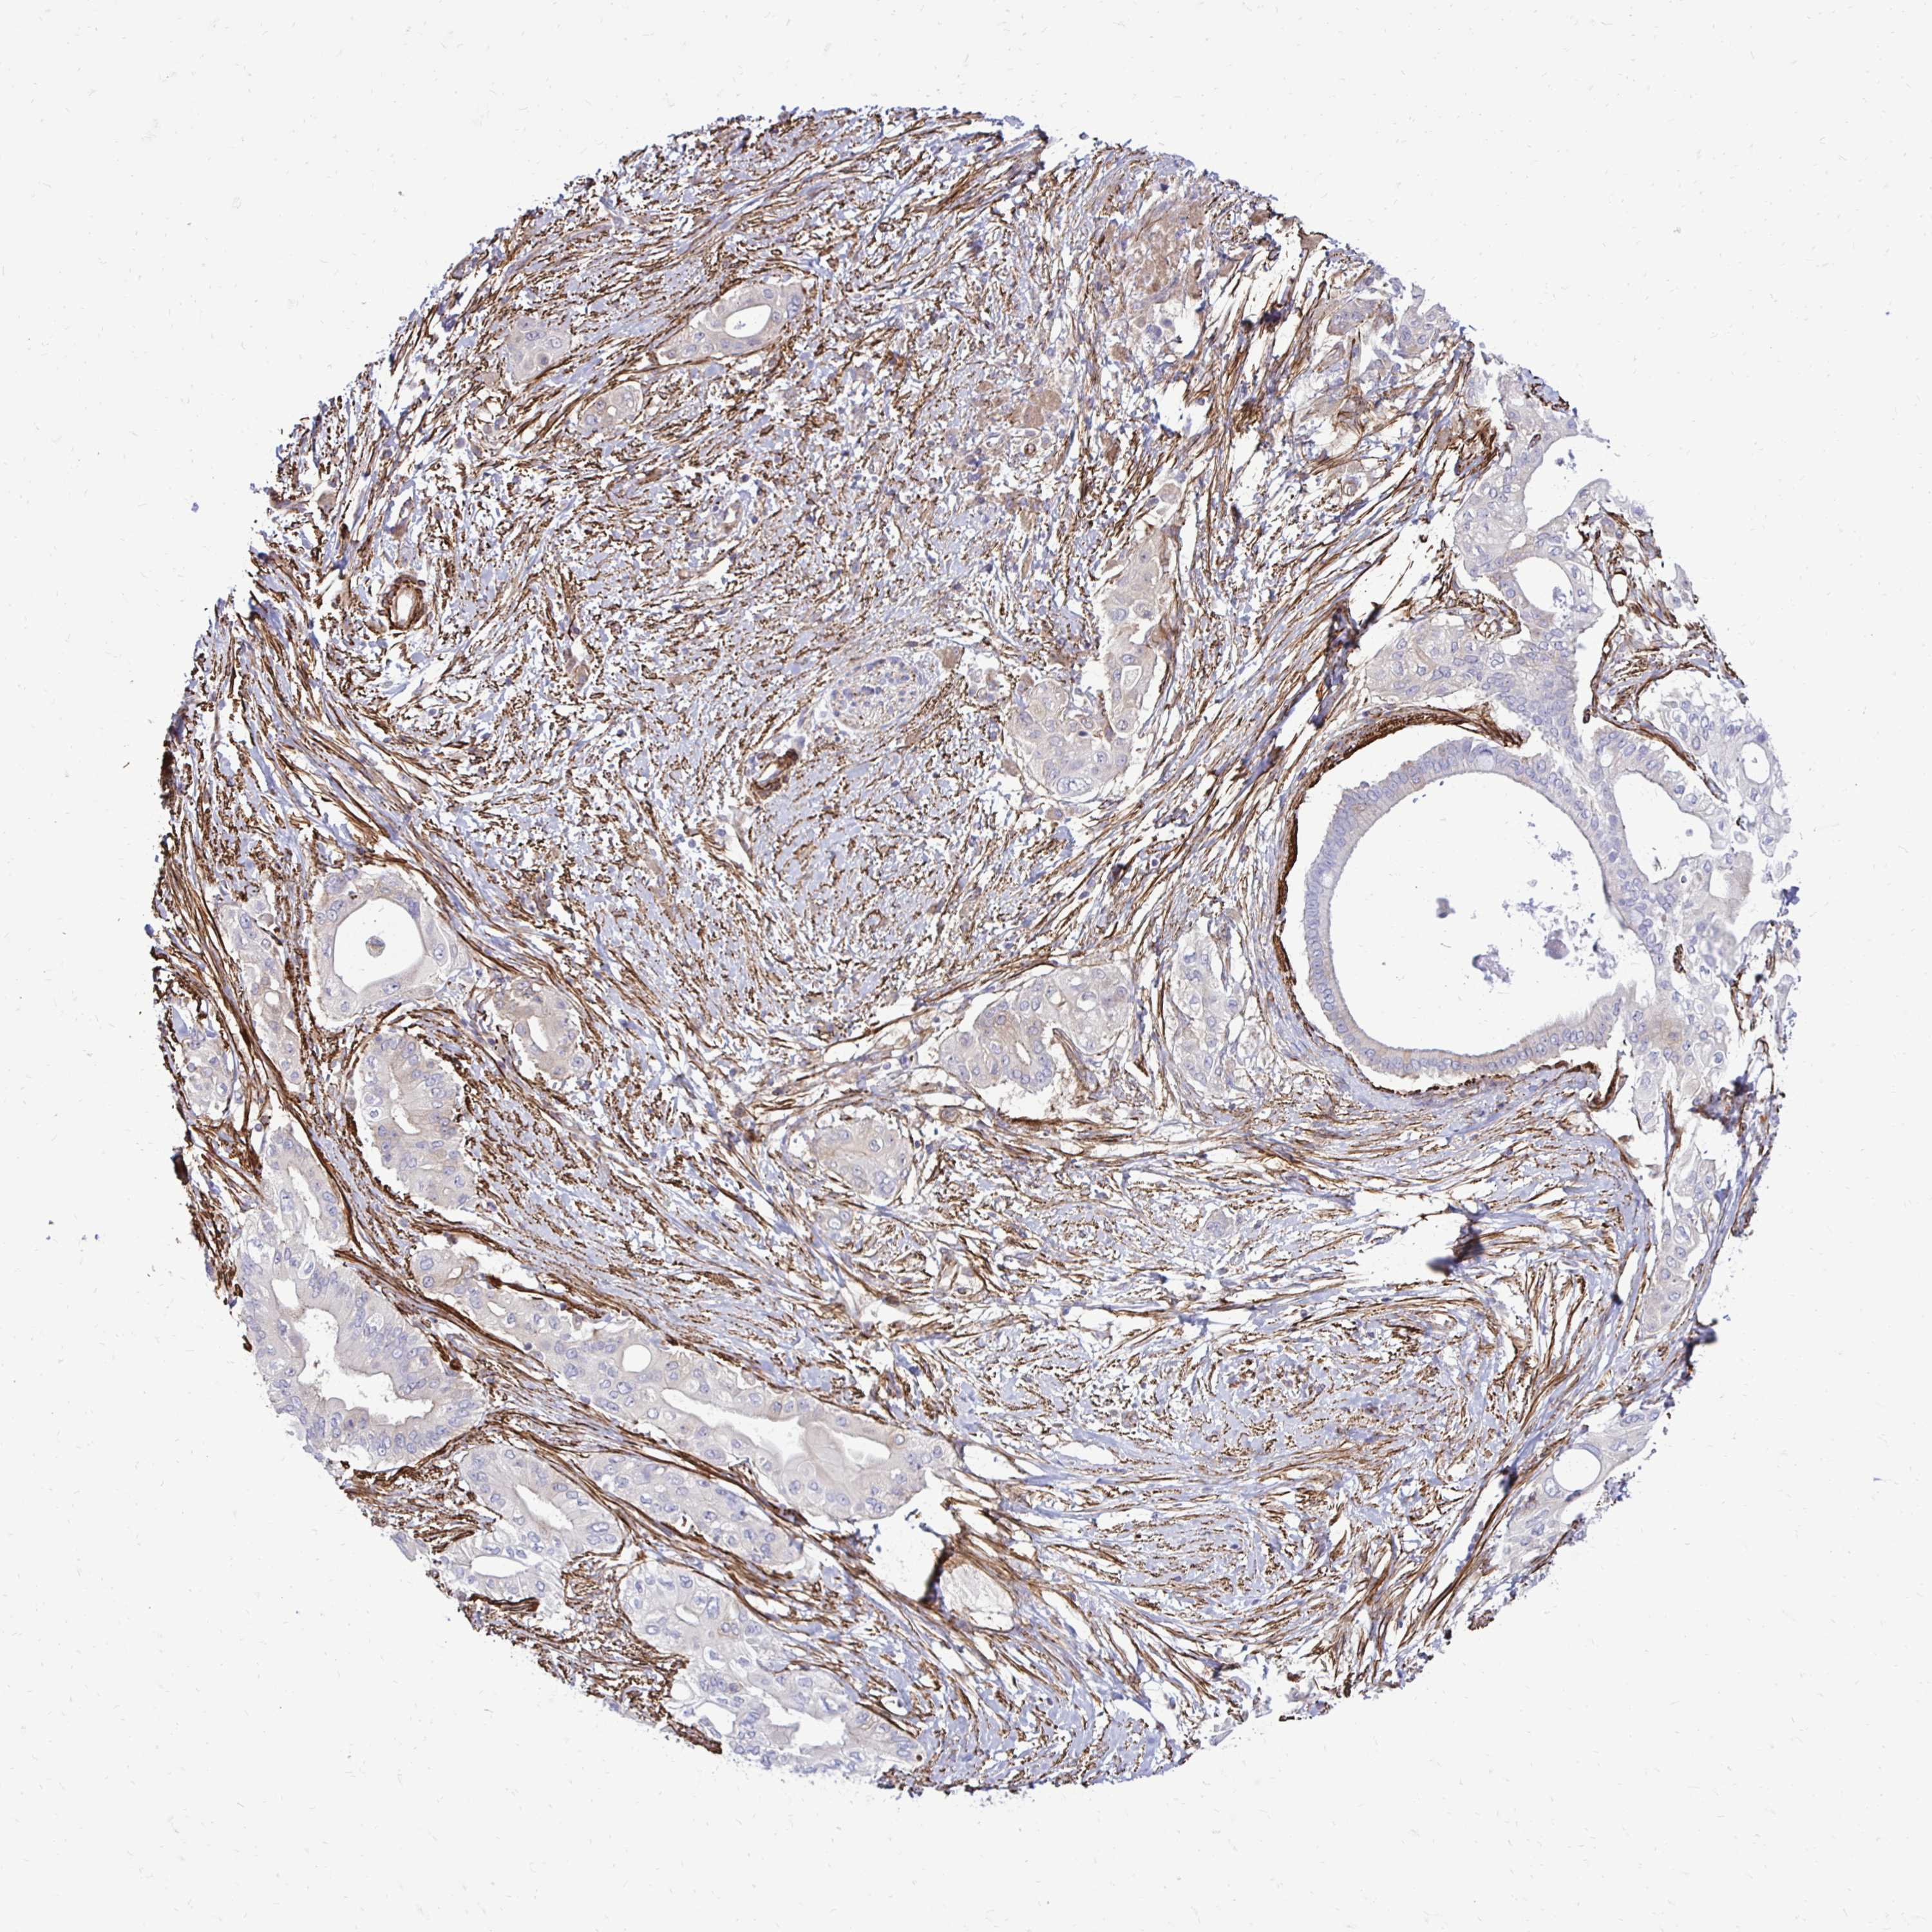

PANCREATIC CANCER - Protein expressioni

A mouse-over function shows sample information and annotation data. Click on an image to view it in a full screen mode. Samples can be filtered based on level of antibody staining by selecting one or several of the following categories: high, medium, low and not detected. The assay and annotation is described here.

Note that samples used for immunohistochemistry by the Human Protein Atlas do not correspond to samples in the TCGA dataset.

Antibody stainingi

Antibody staining in the annotated cell types in the current human tissue is reported as not detected, low, medium, or high, based on conventional immunohistochemistry profiling in selected tissues. This score is based on the combination of the staining intensity and fraction of stained cells.

Each image is clickable and will lead to virtual microscopy that enables deeper exploration of all samples and also displays staining intensity scores, fraction scores and subcellular localization as well as patient and tissue information for each sample.

Antibody HPA051322

Antibody CAB017111

Staining

High

Medium

Low

Not detected

Intensity

Strong

Moderate

Weak

Negative

Quantity

>75%

75%-25%

<25%

None

Location

Nuclear

Cytoplasmic/membranous

Cytoplasmic/membranous,nuclear

Adenocarcinoma, NOS